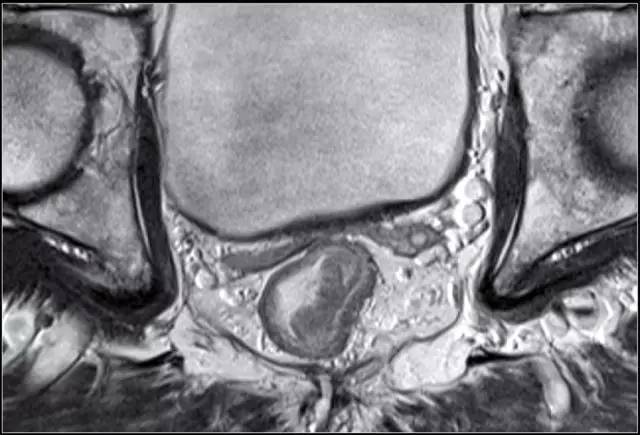

图 5 远端直肠半圆形 T2 肿瘤,与外部肌层分界明显

MR 无法区分肿瘤是局限于黏膜下层还是浸润至固有肌层,直肠内超声(US)能够更准确地区分 T1 和 T2。T1~2 期肿瘤未穿透肠壁,预后较好,T1~2 期 MRI 上可见直肠肠壁完整的黑色边界。